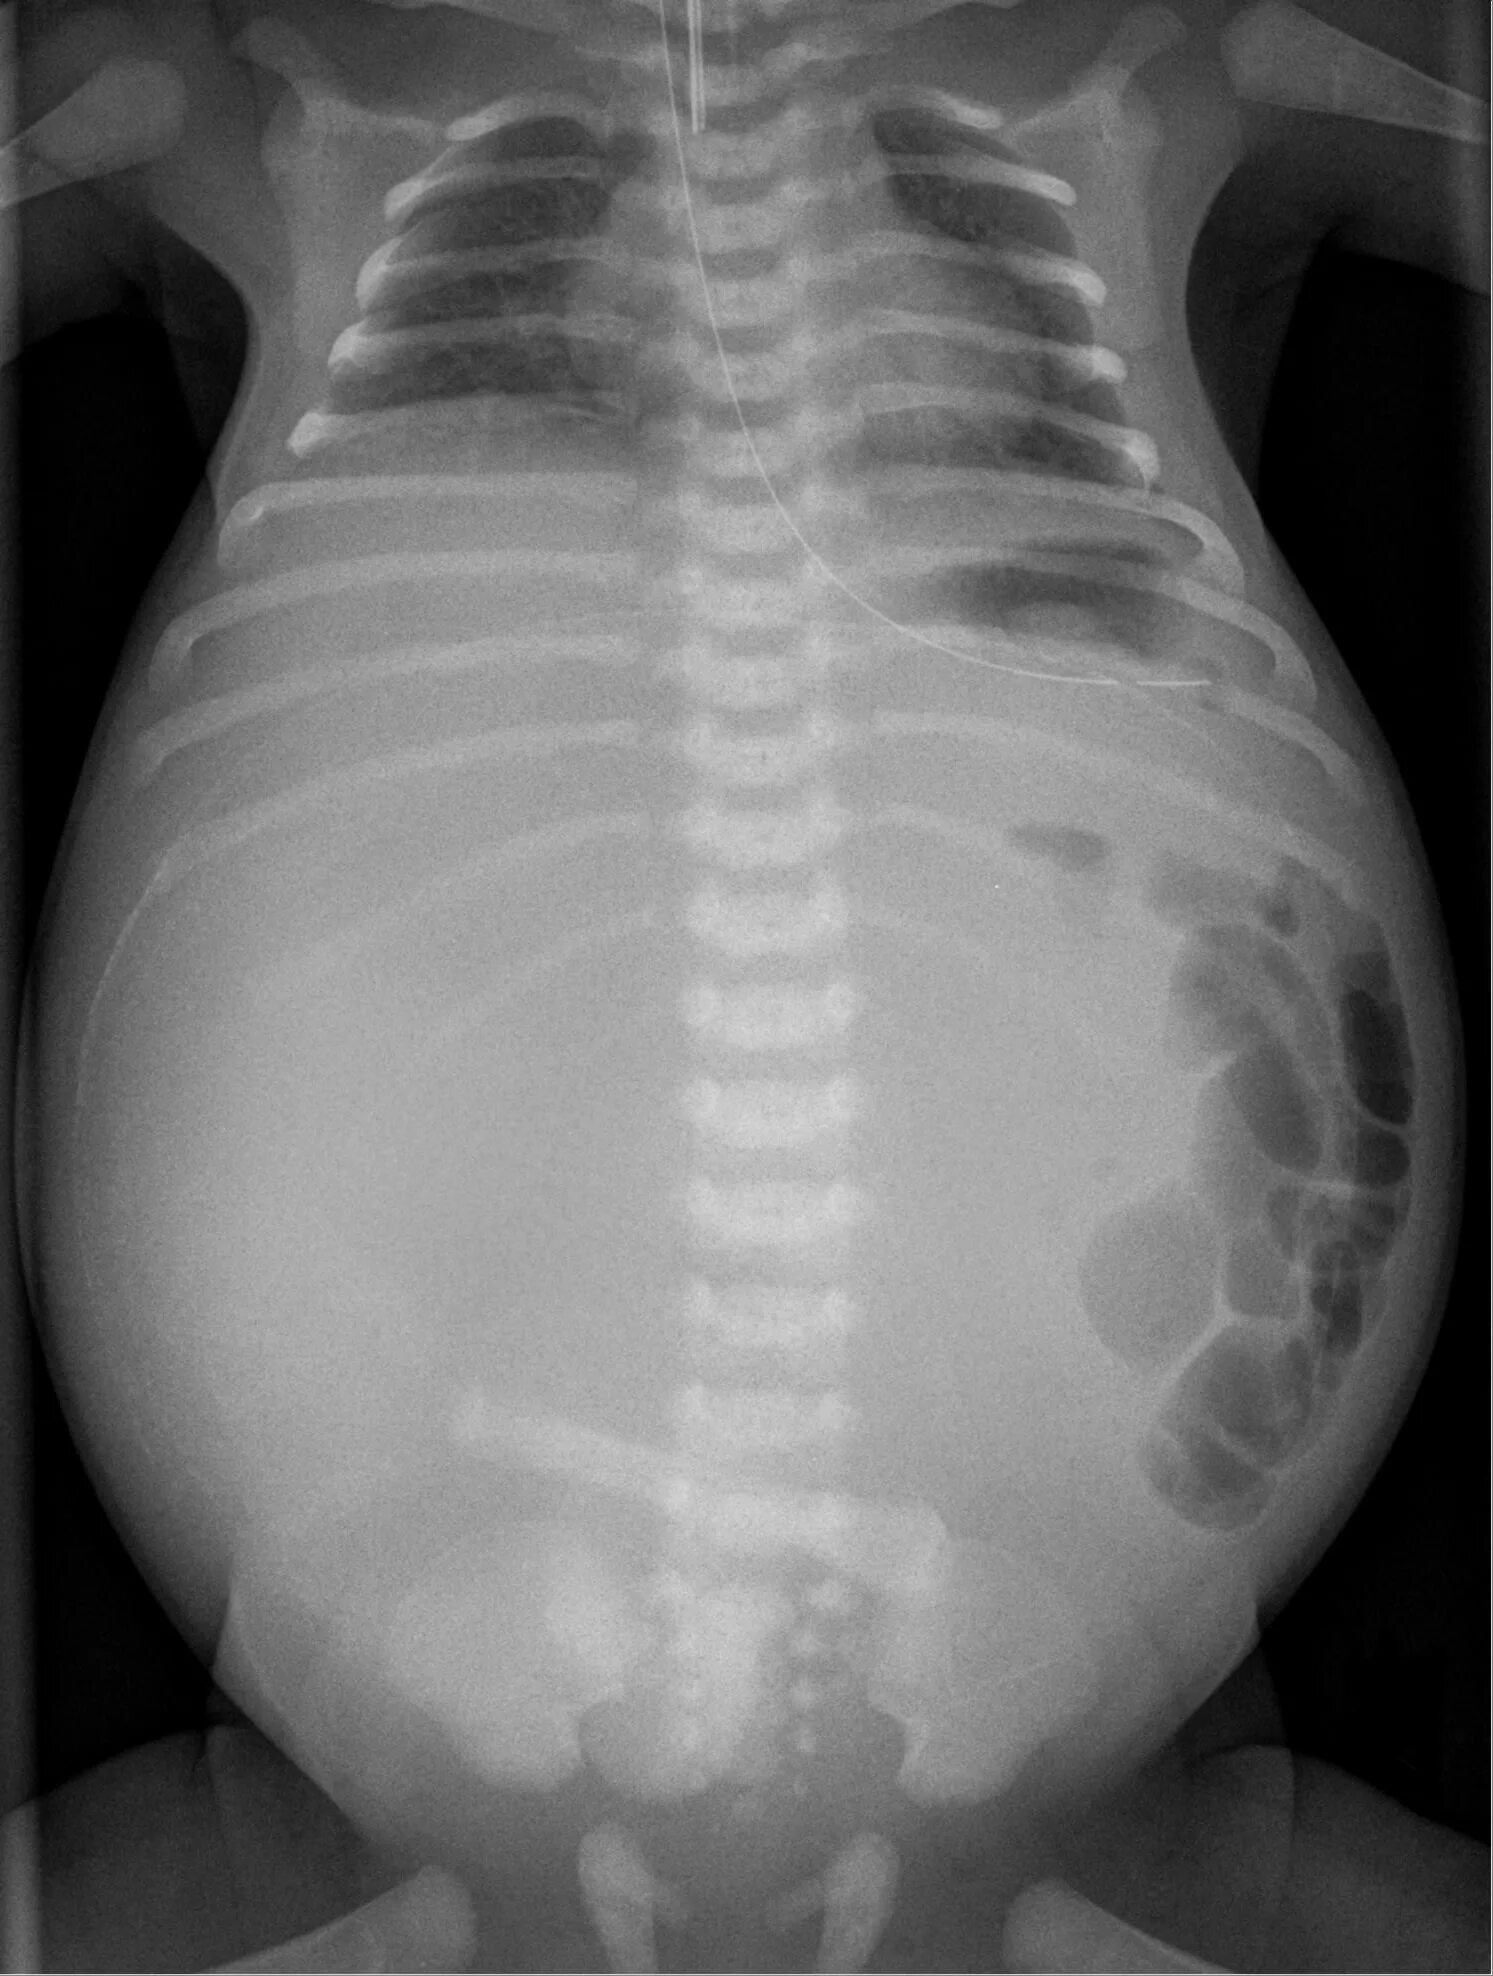

Асцит в малом тазу